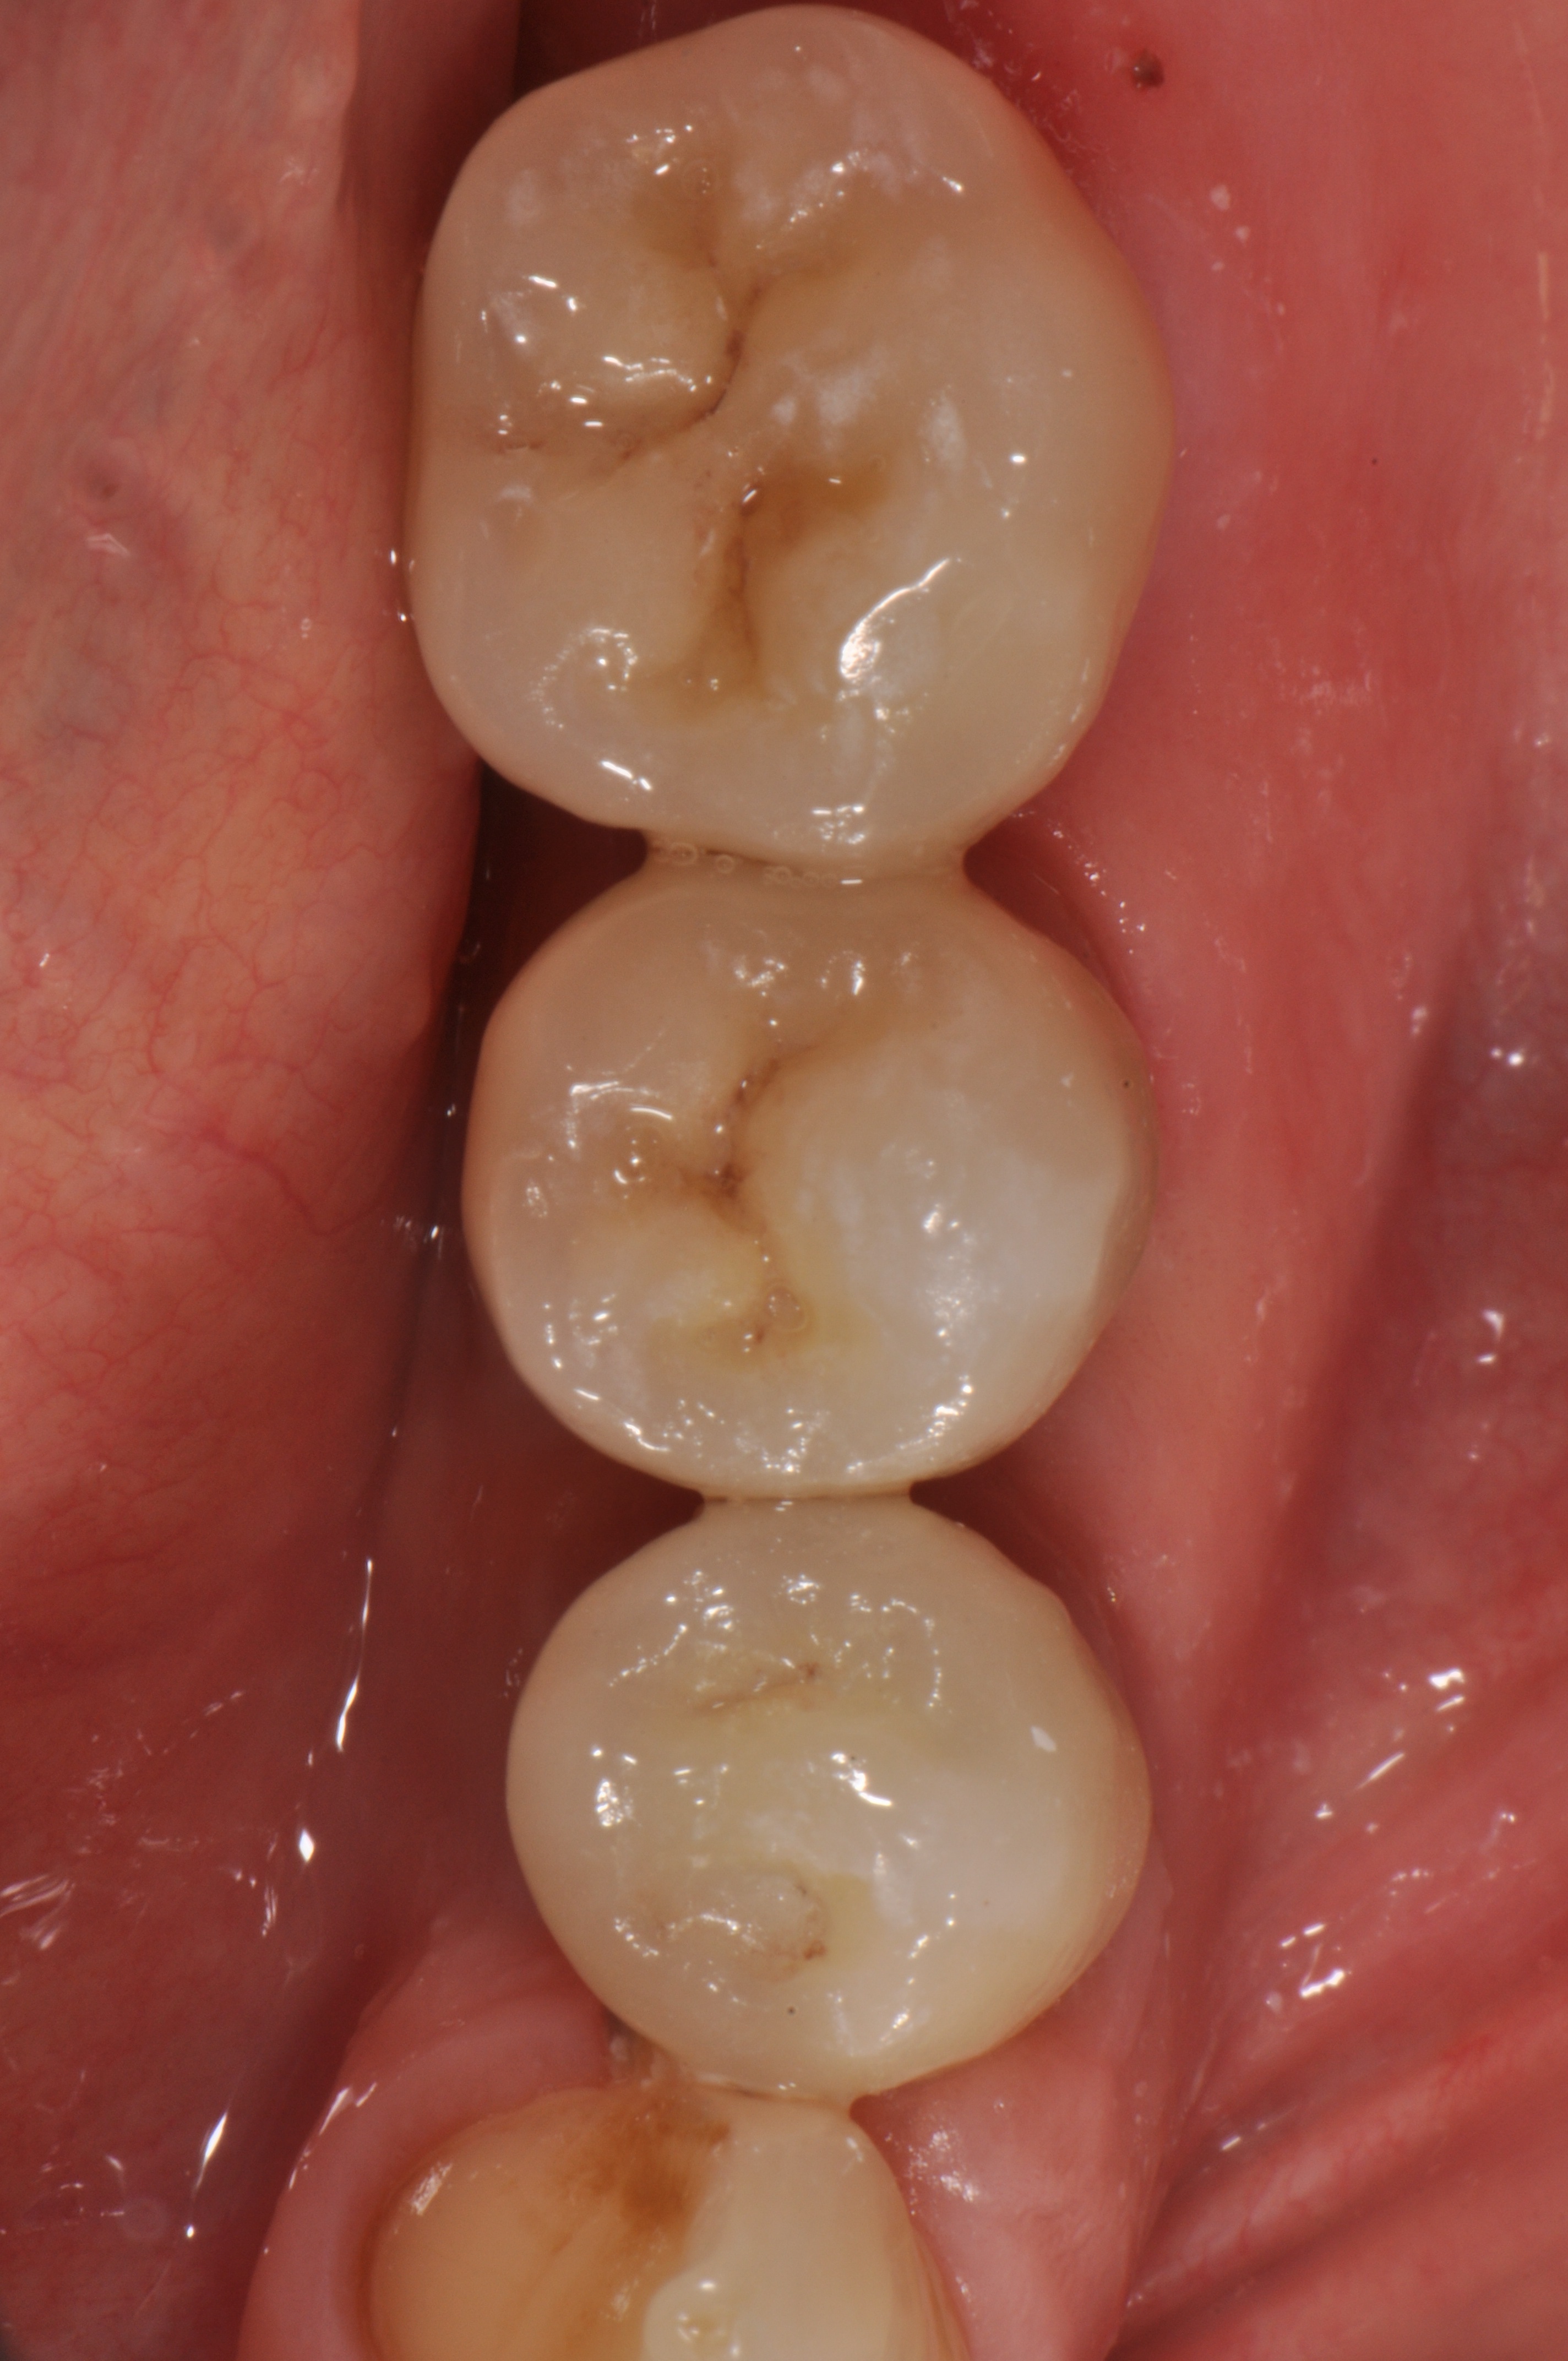

A 52-year-old patient is a referral and has been wearing an immediate provisional partial denture after replacement of her worn and fractured fixed partial denture. As a definitive treatment solution, the patient desired "beautiful and long-lasting" implant-supported single crowns. Clinically the CT-scan revealed a very narrow bone crest ("knife-edge") in the 3rd quadrant. Implant placement has been planned with a simultaneous GBR procedure.